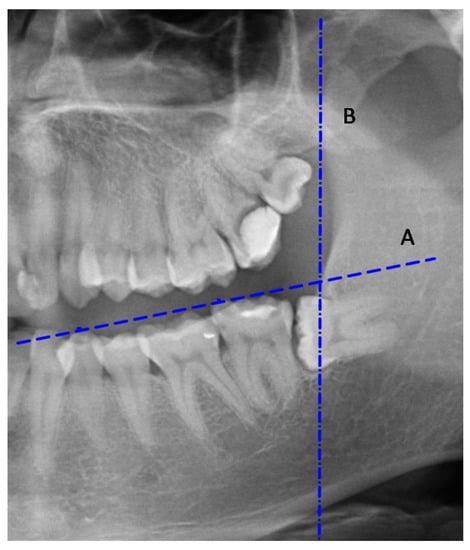

2.1.1. Plotting the Lines Necessary to Evaluate the Impaction of an Impacted Mandibular Third Molar

- Long axis of the tooth (a);

- Occlusal plane (A);

- Tangent to the anterior margin of the mandibular ramus (B).